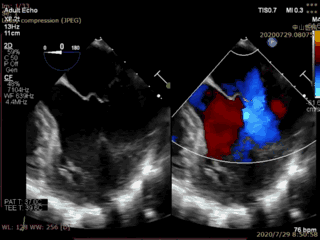

本例患者是一名70岁男性,术前超声心动图显示二尖瓣后叶冗长(前叶长度26mm,后叶长度20mm),瓣环前后径32mm,后叶p2关闭脱垂、连枷(脱垂宽度16mm,反流面积23.5cm2)。如此广泛的脱垂,使用国外同类产品完成经导管二尖瓣修复也是有极大挑战,经葛均波院士团队评估,多学科充分讨论后决定为该患者实施Valve Clamp二尖瓣夹合术。

首先在食道超声引导下,植入1枚IIIs型二尖瓣夹合器,释放后显示二尖瓣后叶仍有脱垂连枷,反流为轻中度,为改善患者远期疗效,遂再次植入1枚IIs型二尖瓣夹合器于A2P2的后瓣残余分流处,复查超声显示二尖瓣反流完全消失(0级),整个手术切口出血量几乎为零,手术取得圆满成功。